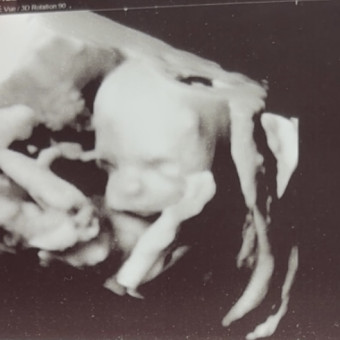

A little cowboy is on the way! It’s a boy and we are so excited to meet our little man. Waylon Caine Gruesbeck you are so loved.

Baby Shower is July 25, 2026A little cowboy is on the way! It’s a boy and we are so excited to meet our little man. Waylon Caine Gruesbeck you are so loved.